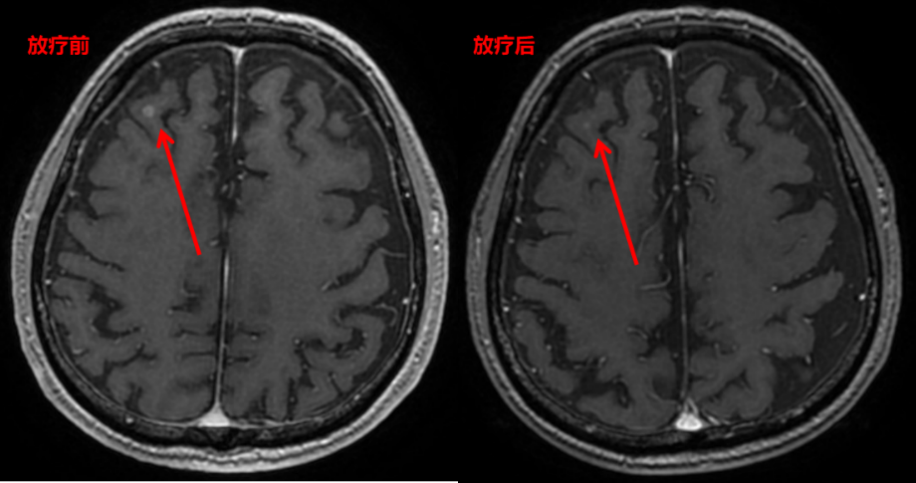

局部治疗:免疫维持治疗20周期后,2024.4复查颅脑MRI提示右侧额叶异常强化结节(新见),考虑转移瘤,因考虑为颅内寡病灶进展,请放疗科会诊后行颅脑姑息放疗。

图片22.png

影像学检查图像(颅脑放疗前、放疗后)

在一线免疫联合化疗的过程中,患者在3周期后即达到PR的疗效,肿瘤标志物显著下降,体现了斯鲁利单抗联合化疗一线治疗方案具有强效的抗肿瘤治疗效果,6周期后疗效评价维持PR,后续予单药免疫维持治疗至今已达3年,展现出斯鲁利单抗持久且稳健的肿瘤控制潜力。此外,在整个治疗过程中,多学科的治疗也起到非常重要的辅助。在整个治疗期间,患者经历了3次的局部放疗。第一次腰椎骨转移病灶的姑息放疗,减轻了患者的疼痛症状、提高了生活质量。第二次胸部及淋巴结病灶的局部放疗,增加了肿瘤的局部控制率。第三次脑转移病灶的调强放疗,达到了局部寡转移病灶的控制。多学科的综合治疗,使患者在长期随访过程中总体疗效评价仍维持PR,达到3年的长生存,远超预期。同时,该患者治疗过程中出现肾上腺皮质功能减退,予以对症处理后临床可控,且未见其他免疫治疗相关不良反应,整体安全性良好,较好地保障了患者免疫治疗的长期顺利进行。